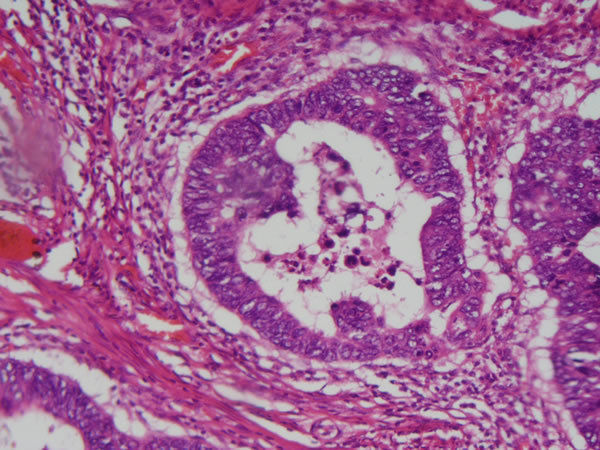

Intestino grosso - Epit. cilíndrico simples Inflamação crônica granulomatosa- granuloma por esquistossomose (form tumoral) Causas: Infecções persistentes, reação de hipersensibilidade, exp. agentes tóxicos |